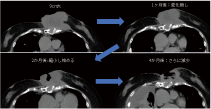

当院のBNCT症例

写真内の電子捕獲は一貫しています。CT では捉えられない播種の例が再発病変の周囲で見つかりました。 この種の再発病変は通常乳がんですが、病変の範囲を特定するのは容易ではなく、放射線治療、陽子線、重粒子線は適していません。

BNCT は巨大な腫瘍を治療できます。ただし、他の放射線療法と同様、画像検査で腫瘍が縮小し始めるのは治療後 2 か月目以降です。